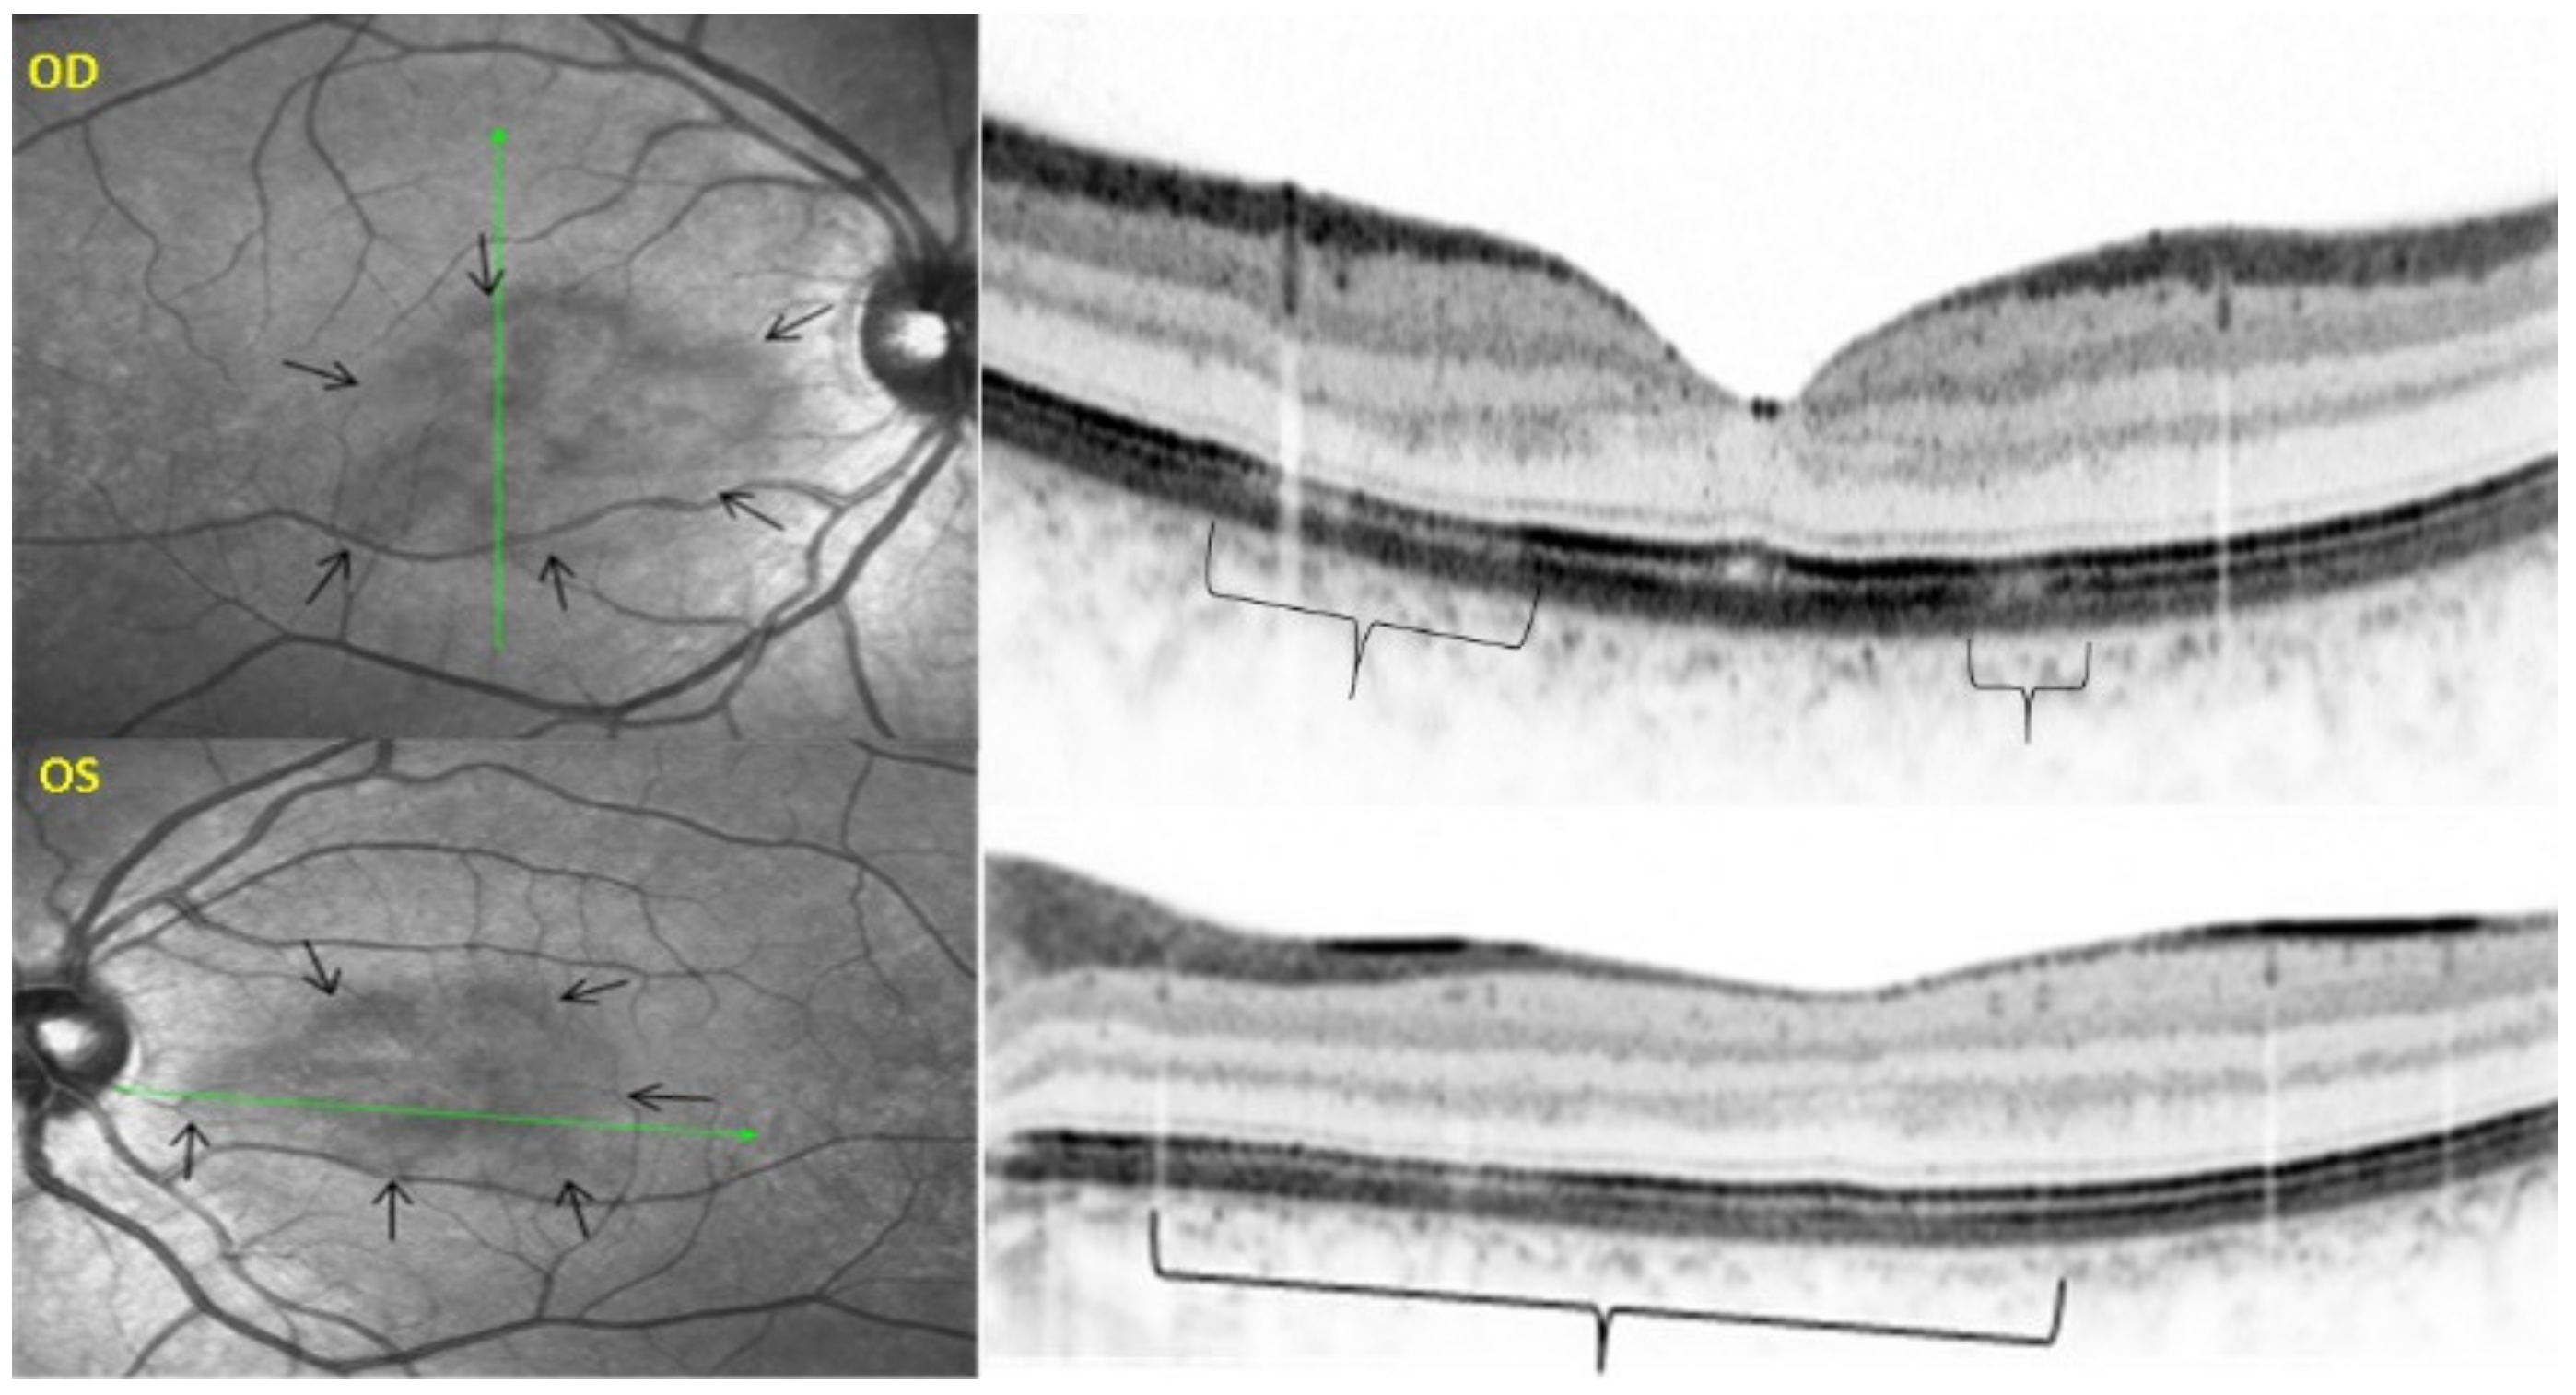

Among the multimodal imaging approach, ICGA is the most important investigation allowing early diagnosis and precise follow-up [118]. The main features seen in the acute phase of the disease are the presence of disseminated, even, regularly distributed hypofluorescent dark dots (HDDs) in the intermediate and late angiographic phases (Figure 49), accompanied by the usual angiographic signs of stromal choroiditis (Table 1). However, in VKH, ICGA disc hyperfluorescence is much more frequent because of the hyperacute character of the disease. In case of exudative detachments, ICGA shows the same hyperfluorescent pinpoints seen on FA. These signs all regress with treatment. In that regard, ICGA was found to be essential in the follow-up of the disease.

On FA, serous exudative detachments occurring in the acute early stage appear as multifocal hyperfluorescent pinpoints, showing the leaking points at the level of pigment epithelium also seen on ICGA, with late pooling of the dye in the subretinal space (Figure 48). Optic disc staining also appears in the acute phase. However, no retinal vasculitis is seen. In the chronic phase, FA clearly shows the diffuse retinal pigment epithelium alterations classically appearing as a mixture of window and masking effects as a consequence of the exudative retinal detachment, the limits of which are well shown and are called highwater marks. In the chronic phase, a hyperfluorescent “hot” disc may be the only FA sign indicating inflammatory activity, whereas ICGA can show subclinical choroidal granulomas, a sign of subclinical inflammatory activity. B-can echography is only of interest in case the media are opacified. OCT gives precious information on the evolution of secondary retinal lesions and EDI-OCT measuring choroidal thickening is a complimentary modality allowing follow choroidal inflammation (Figure 50). VKH being principally a stromal choroiditis OCTA is interesting but does clinically contribute to the practical management of VKH.